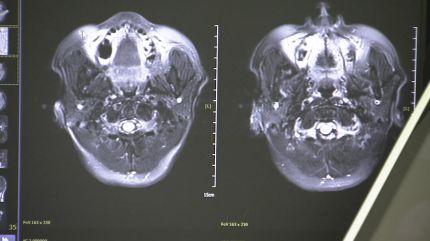

국내 연구진이 무려 13년 동안 2만 명이 넘는 어르신의 혈액을 추적 조사한 끝에, 치매 발병을 예측하는 기술을 개발했습니다.

이런 어르신들을 위해 광주치매코호트연구단은 지난 13년 동안 모두 2만 2천여 명의 생체 빅데이터를 확보했습니다.

증상이 없는 60세 이상 어르신들의 혈액을 채취해 언제 치매에 걸릴지를 예측하기 위해서입니다.

[이건호 / 조선대학교 교수, 광주치매코호트연구단장 : 치매 증세를 나타내게 되면 5년 전, 10년 전 혈액 샘플을 통해서 치매 예측이 가능한지를 직접 확인해 볼 수 있다는 점에서 굉장히 연구의 중요한 의미가 있다고 말씀드릴 수 있습니다.]

[이건호 / 조선대학교 교수, 광주치매코호트연구단장 : 치매 정밀 진단을 통해서 치매 고위험군을 발굴하고 이분들을 대상으로 장기 추적을 해왔기 때문에 이제는 치매 증세가 오기 전에 치매 진행을 예측할 수 있는 기술의 확보가 가능해졌다….]